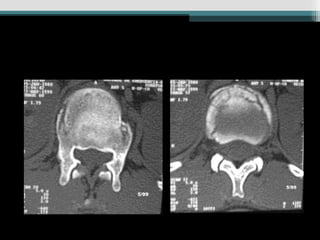

• TC - Visualiza melhor colunas média e posterior ;

fraturas obscuras ; estreitamento canal e

fragmentos ; orienta tratamento cirúrgico ;

útil quando o déficit não corresponder a lesão

(incompleto).